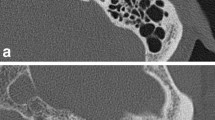

As similar to previous studies [27, 28], radiologist B placed a linear region of interest passing the handle of the malleus on axial image (Fig. 1a). The copy-and-paste function of region of interest was also used in this analysis to ensure that the location and size were identical on the DLR and HIR images. Based on the CT attenuation profile along the region of interest, the edge rise slope [29, 30] was calculated (Fig. 1b).

The edge rise slope in DLR (2571.5 ± 923.1 HU/mm−1) was significantly better compared to that in HIR (2416.0 ± 846.0 HU/mm−1) (p = 0.004).